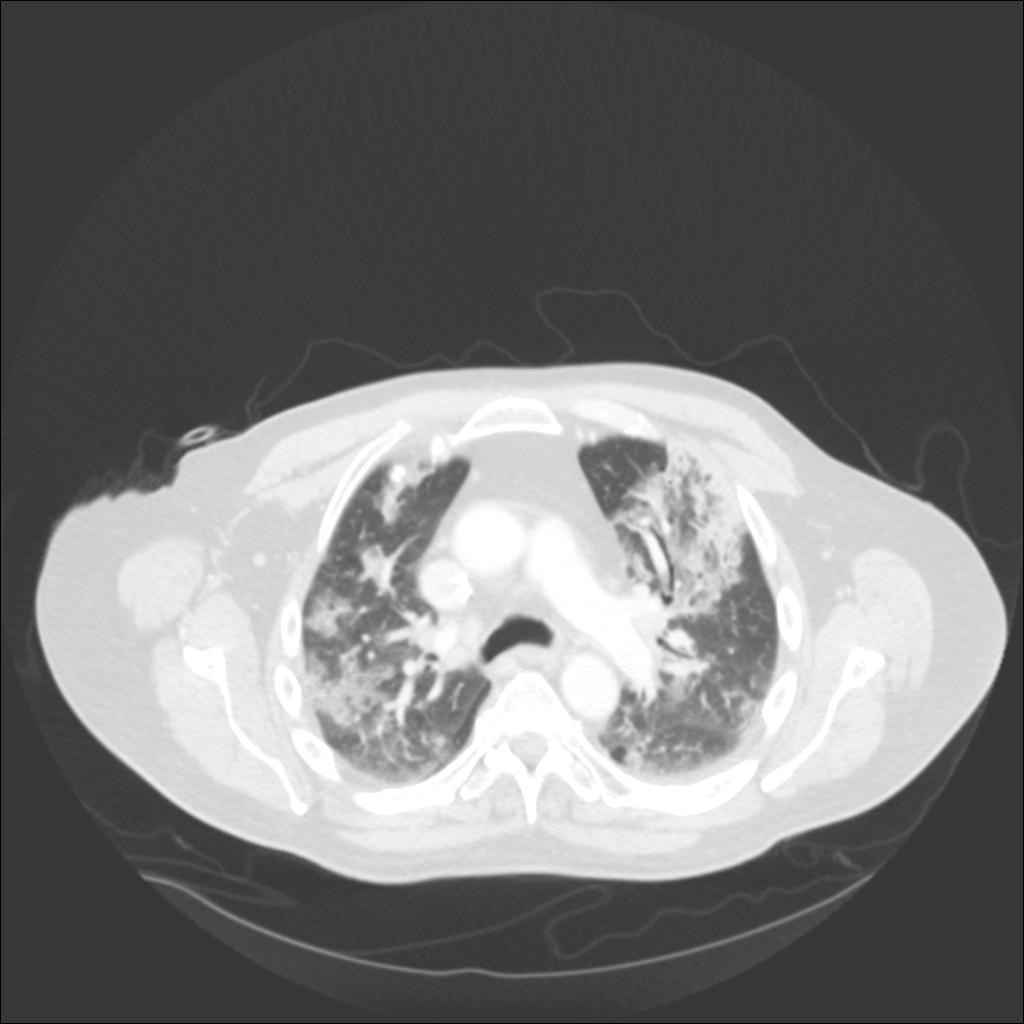

In our patient, the chest radiograph revealed multifocal alveolar infiltrates predominantly in the right upper lobe, left upper lobe, and left lower lobe. Chest CT revealed patchy ground glass and consolidative infiltrates throughout both lungs.